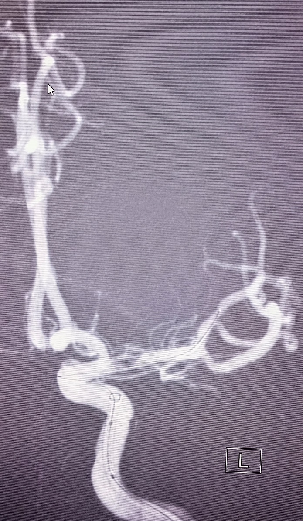

导丝怎么扩【载药时代 球扩天下】NOVA DES®颅内药物洗脱支架在大脑中动脉重度狭窄中的应用两例!_https://www.jmylbn.com_新闻资讯_第7张

导丝怎么扩【载药时代 球扩天下】NOVA DES®颅内药物洗脱支架在大脑中动脉重度狭窄中的应用两例!_https://www.jmylbn.com_新闻资讯_第8张

颈动脉支架释放

在微导丝辅助下将2.25*10mm赛诺神畅颅内药物洗脱支架NOVA DES®于大脑中动脉狭窄处扩张成形术。